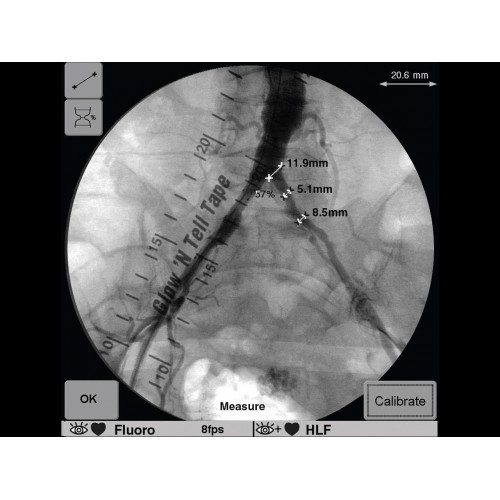

Инновационная мобильная С-дуговая система для интраоперационной визуализации с высоким разрешением. Обеспечивает хирургов качественным изображением в реальном времени при минимальной лучевой нагрузке. Усовершенствованная эргономика позволяет легко позиционировать аппарат в условиях операционной. Поддерживает интеграцию с современными хирургическими навигационными системами.

GE OEC 9900 Elite оснащен революционной системой визуализации, обеспечивающей кристально четкое изображение анатомических структур. Интеллектуальная система автоматически адаптирует параметры исследования под конкретную хирургическую задачу, обеспечивая оптимальный баланс между качеством изображения и лучевой нагрузкой. Особое внимание уделено удобству работы операционной бригады.

В операционной практике GE OEC 9900 Elite демонстрирует исключительную эффективность при проведении сложных малоинвазивных процедур. Оборудование позволяет значительно сократить время вмешательства и повысить его безопасность для пациента. Многие хирурги отмечают улучшение точности операций и комфорт работы с системой.

В ведущих медицинских центрах GE OEC 9900 Elite успешно применяется для проведения сложных кардиологических, нейрохирургических и ортопедических вмешательств. Система доказала свою эффективность при выполнении стентирования коронарных артерий, эмболизации сосудов головного мозга и вертебропластики. Многие учреждения отмечают повышение качества операций после внедрения этого оборудования.